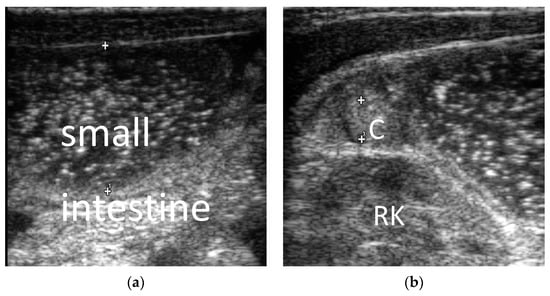

3.2. The Ultrasonic Manifestations

3.2.1. The Ultrasonic Signs of Intestinal Obstruction

3.2.2. The Corresponding Ultrasound Findings of Diseases Leading to Neonatal Ileus